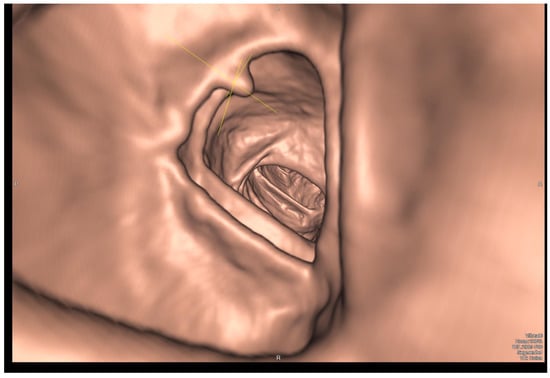

5. Virtual Colonoscopy (CTC)